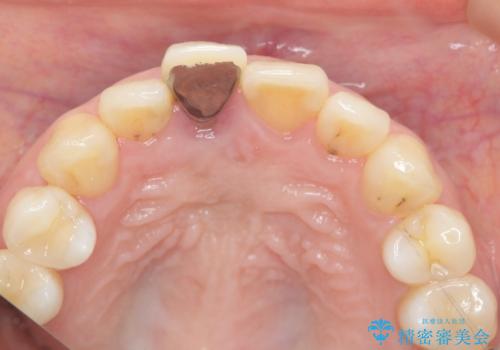

- 幼少期に前歯をぶつけて歯が折れ、神経の治療・クラウン治療を行った。グラつきと見た目の改善を希望して来院されました。

精密な仮歯をいれ、歯周組織を整えるとともにファイバーコア築盛、シェードテイキングを行い見た目に自然なジルコニアクラウンを製作していきます。

- 16万円(仮歯・ファイバーコア・ジルコニアクラウンスペシャル)費用は治療当時の料金となります